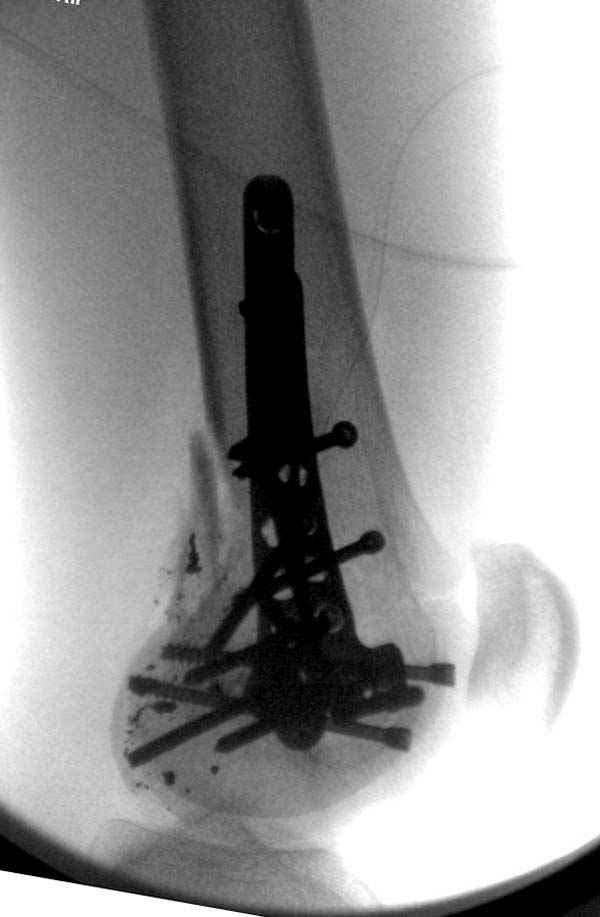

Если идет речь о классификации ран по Gustilo, тогда трудно согласиться с Вашей оценкой, там рана меньше 1 см и подходит больше к первой степени. Такие переломы можно фиксировать любым методом включая пластины и интрамедуллярный способ.

Здесь применен рутинный метод лечения огнестрельных переломов, т.е. рана теоретически чистая, что противоречит принятым ранее догмам . По принятой тактике, при огнестрельных переломах назначаются антибиотики Ancef 1gm каждые 8 часов внутривенно в течение 24 часов. Желательно первую дозу ввести непосредственно перед разрезом.

Переломы с ранами по Gustilo IIIA, согласны, подлежат к отсроченной фиксации после первичной стабилизации в аппарате наружной фиксации.

Сустав не дренировался, но медиально перед закрытием раны под фасцией уложен дренаж Hemovac, который удален через 24 часа.

Менее 30 миллилитров за последнее 3 часа - показания к удалению дренажной трубки. И тут есть свои тонкости. Есть данные, что в дренажной трубке работают 4 самых дистальных отверстия. Остальные обычно <забиваются> и способствуют возникновению тромбов и сгустков фибрина, что может явиться причиной <неработающей> дренажной системы.

Если больной продолжает оставаться в больнице, то после удаления дренажа назначаются реабилитация-разработка сустава на CPM (аппарат для принудительной разработки суставов) с увеличением амплитуды на нарастание.

По Густило и Андерсену все high-energy переломы являются III не зависимо от степени повреждения мягких тканей. Plating такого перелома на второй день кажется немного рискованным хотя "победителей не судят". Судя по КТ, медиальный мыщелок стабильный, насколько необходимо было его фиксировать?

Красиво и быстро?! - две пластины + 18 шурупов.

Идеальная репозиция?! -На снимочке A-P проeкции видна "зазубрина" по суставной поверхности, латеральный снимок - тоже не идеально.

Множество мелких FB в кости.

Выписан через 3 дня после операции - как минимум,надо 7 дней i.v. антибиотикотерапию.

Даже если не возникнет септических осложнений, скорей всего исход - нетрудоспособность(disability).

IMHO- ПХО,активный дренаж, и если не аппарат наружной фиксации,то даже вытяжение за бугристость б/б кости.